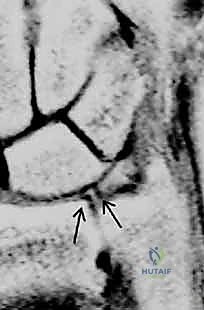

- Utility: MRI is a valuable tool for diagnosing TFCC tears, particularly Class 1A (central) and 1D (radial avulsion) lesions.

- Sequences: T2-weighted images in the coronal plane offer the greatest diagnostic value. The TFCC normally exhibits a homogenous low signal intensity. Synovial fluid appears as a bright signal on T2-weighted images and will outline tears within the TFCC.

* MR Arthrography: Injecting gadolinium into the joint enhances the visualization of TFCC tears, improving sensitivity and specificity compared to conventional MRI. However, even with arthrography, negative results in a patient with strong clinical suspicion should be interpreted with caution.

* Sensitivity & Specificity: The reported sensitivity and specificity of MRI for TFCC tears vary widely in the literature (e.g., sensitivity 44-95%, specificity 75-95%). While useful, MRI findings do not always perfectly correlate with arthroscopic findings.